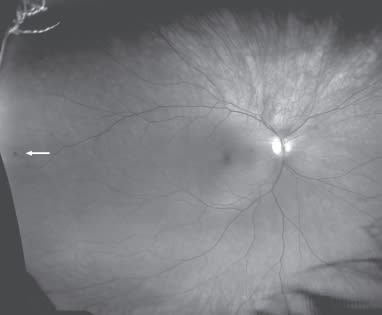

Figure 1. Retinal tear

Dr. Rothschild: I recently examined our office manager's husband, a healthy young man with no vision complaints. He came in because his wife convinced him to get an exam. The optomap revealed a peripheral retinal tear. We sent him to the retinal surgeon, who performed laser surgery.